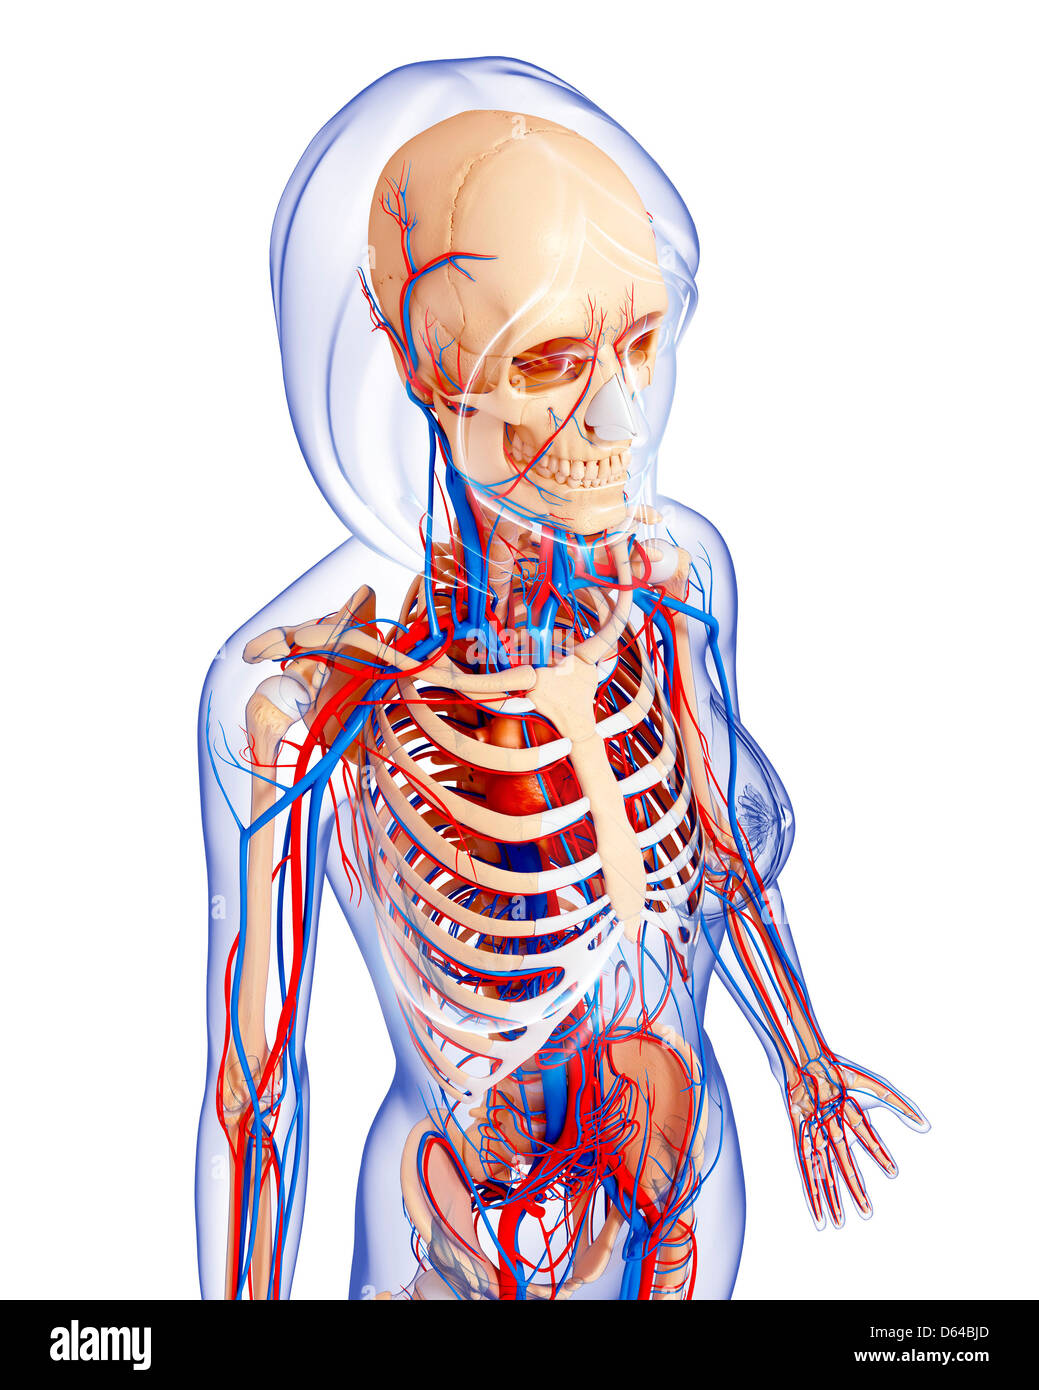

fineartamerica.comFemale Anatomy, Artwork Stock Photo - Alamy

fineartamerica.comFemale Anatomy, Artwork Stock Photo - Alamy

fineartamerica.comFemale Anatomy, Artwork Stock Photo - Alamy

fineartamerica.comFemale Anatomy, Artwork Stock Photo - Alamy

bocadowasubo.github.ioFemale Anatomy, Artwork Stock Photo - Alamy

bocadowasubo.github.ioFemale Anatomy, Artwork Stock Photo - Alamy

www.etsy.comFemale Anatomy, Artwork Stock Photo - Alamy

www.etsy.comFemale Anatomy, Artwork Stock Photo - Alamy

Female Anatomy, Artwork Stock Photo - Alamy

www.alamy.comFemale Anatomy, Artwork Stock Photo - Alamy

Female Anatomy, Artwork Stock Photo - Alamy

www.alamy.com3d Rendered Illustration Of The Female Anatomy Stock Photo - Alamy